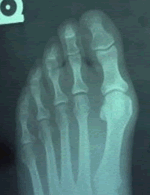

Bunion DeformityOne of the more common conditions treated by podiatric surgeons is the painful bunion, i.e. a painful bump on the inside and base of the big toe together with a crooked big toe. Patients with this condition will usually complain of pain when wearing certain shoes, especially snug fitting dress shoes, or with physical activity, such as walking or running. There are several surgical procedures to correct bunions. Selection of the most appropriate procedure for each patient requires a thorough examination of the patient and a review of weight-bearing x-rays of the foot. All surgical procedures require cutting and repositioning the first metatarsal, and sometimes the bones of the big toe itself.

The classic bunion, medically known as Hallux Abducto Valgus or HAV, is a bump on the side of the great toe joint. This bump represents a thickening of the joint tissues and the underlying bone on the inside of the metatarsal head, the bone that joins the big toe at its base. In addition, there is also deviation of the great toe toward the second toe. In severe cases, the great toe can either lie above or below the second toe. Shoes are often blamed for creating these problems. This, however, is inaccurate; In places where people do not wear shoes, the statistical chance of a crooked big toe is the same.

Bunions develop from abnormal foot structure and poor mechanics of the foot. This leads to stretching of supporting soft tissue structures such as joint capsules and ligaments with the end result being gradual deviation and dislocation of the big toe, which then pushes back against the 1st metatarsal head making it stick-out. As this deformity increases, there is an abnormal pull of certain tendons, which leads to the drifting of the great toe toward the 2nd toe more-and-more. This cycle continues until the big toe almost completely dislocates off of the 1st metatarsal head.

Early treatment of all bunions is centered on providing symptomatic relief. Switching to a shoe with a rounder, deeper toe box and made of a softer more pliable leather will often provide immediate relief. When these conservative measures fail to provided adequate relief, surgical correction is indicated. The choice of surgical procedures is based on a biomechanical and radiographic examination of the foot. Because there is structural malalignment of bones and joint(s), successful correction can only be achieved cutting and realignment of bone(s) and soft tissues. Simply "shaving the bump" is grossly inadequate in providing correction and in will almost always cause the bunion to remain and then actually become worse. There is no "common" or best type of procedure(s). Each person's foot is special. The surgeon must simply be able to perform whatever procedure or combination is necessary to do the very best job. Bones that are cut and realigned are held-in-place by screws and soft-tissues are sutured in place. 50% of patients will be able to bear some weight on their foot after surgery while the other 50% will have to use crutches for 6 to 8 weeks.